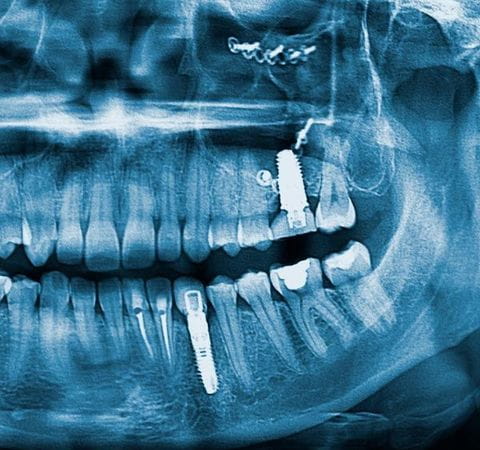

A diferencia de la radiografía dental tradicional, la tomografía permite distinguir las diferencias entre los tejidos y al ser tridimiensionales, se pueden visualizar los planes axiales, coronales y sagitales